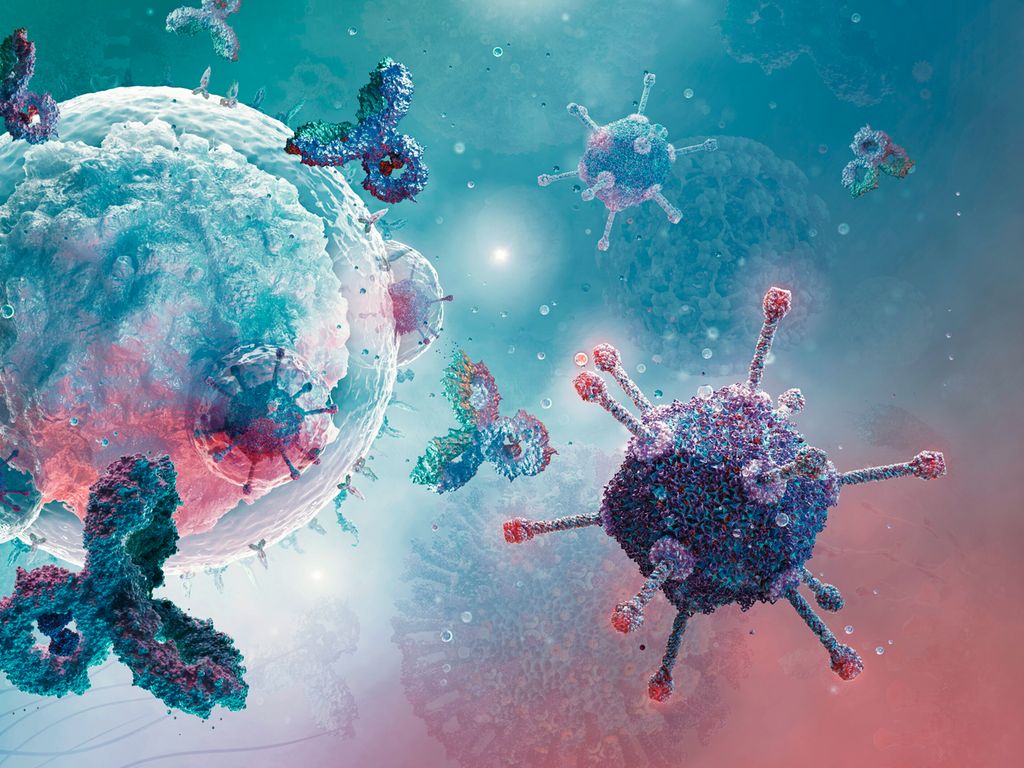

Diffuses großzelliges B-Zell-Lymphom (DLBCL)

Onkologie | Hämatologie

| gültig bis Juni 2026

Onkologie | Hämatologie